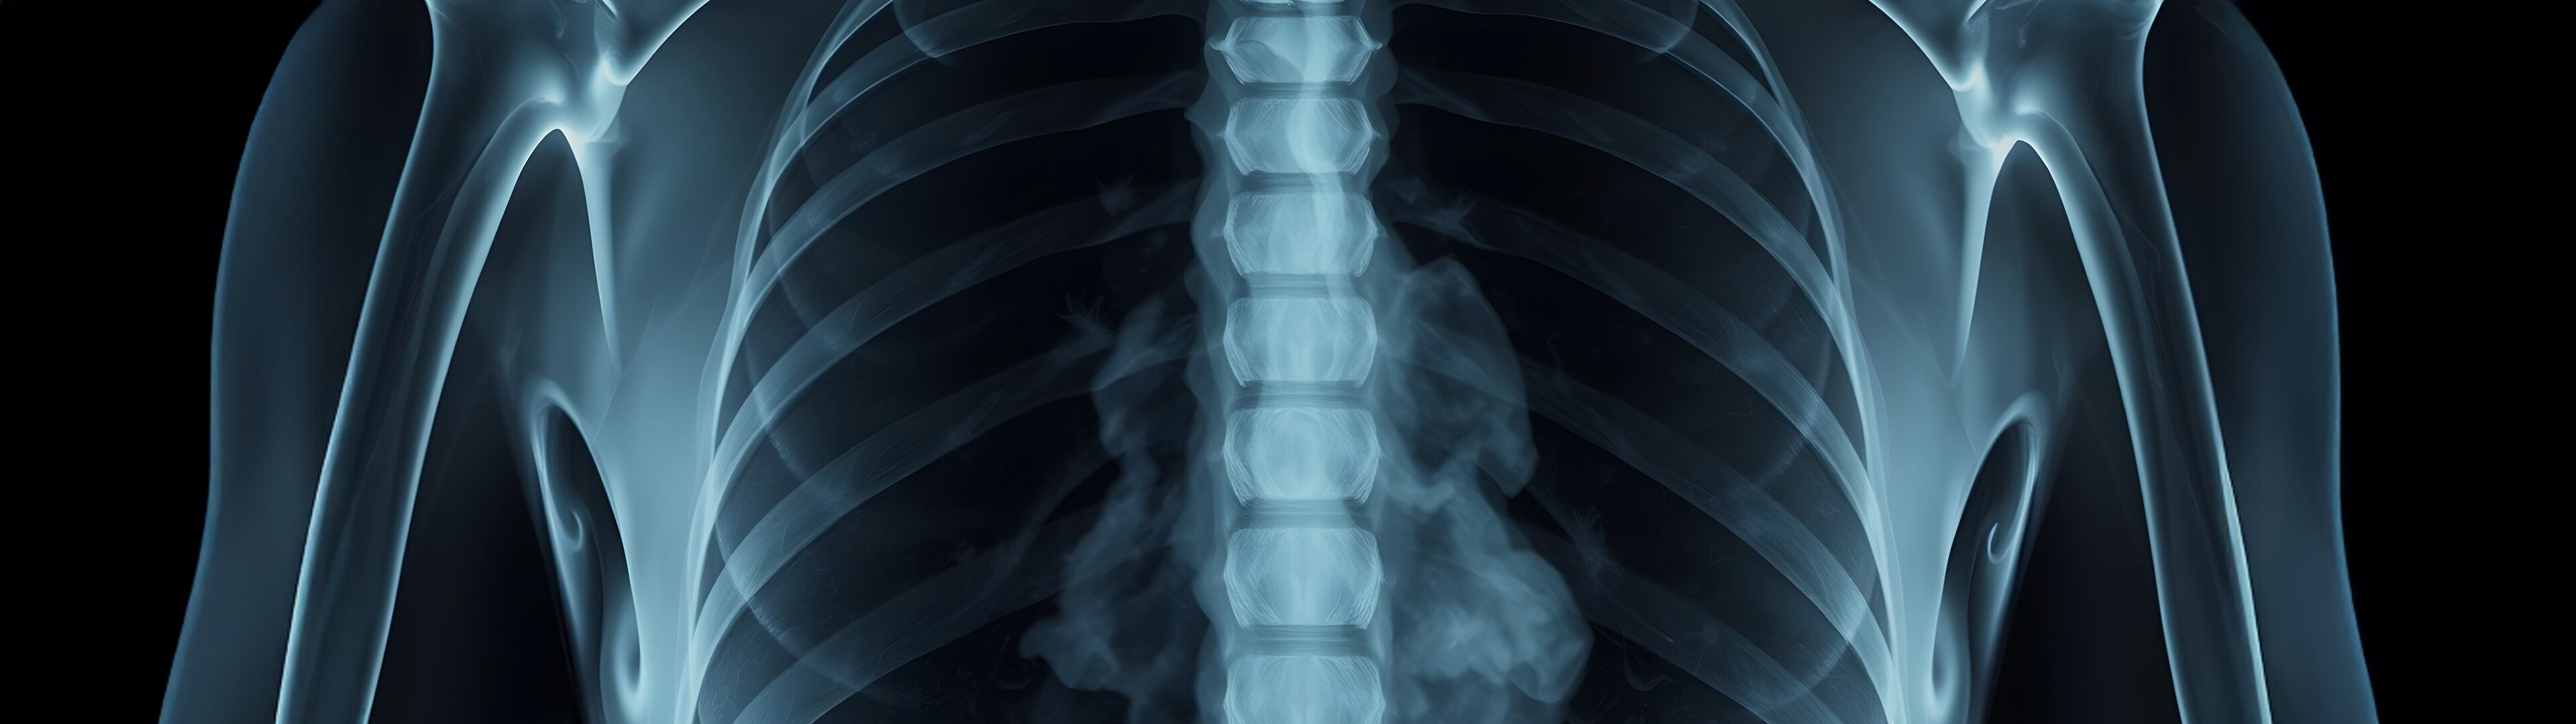

Bei der Weichteilverkalkung – z. B. in der Schulter – lagern sich Kalziumsalze in Sehnen oder Muskeln ab. Dies führt zu starken Schmerzen, Schwellungen und Bewegungseinschränkungen.

Bei einer Weichteilverkalkung – z. B. in der Schulter – lagern sich Kalziumsalze in Sehnen oder Muskeln ab. Das führt zu Schmerzen, Schwellung und Bewegungseinschränkungen. Wenn konservative Therapien wie Physiotherapie oder Injektionen nicht helfen, kann die Strahlentherapie Entzündungen hemmen und die Beschwerden wirksam lindern.